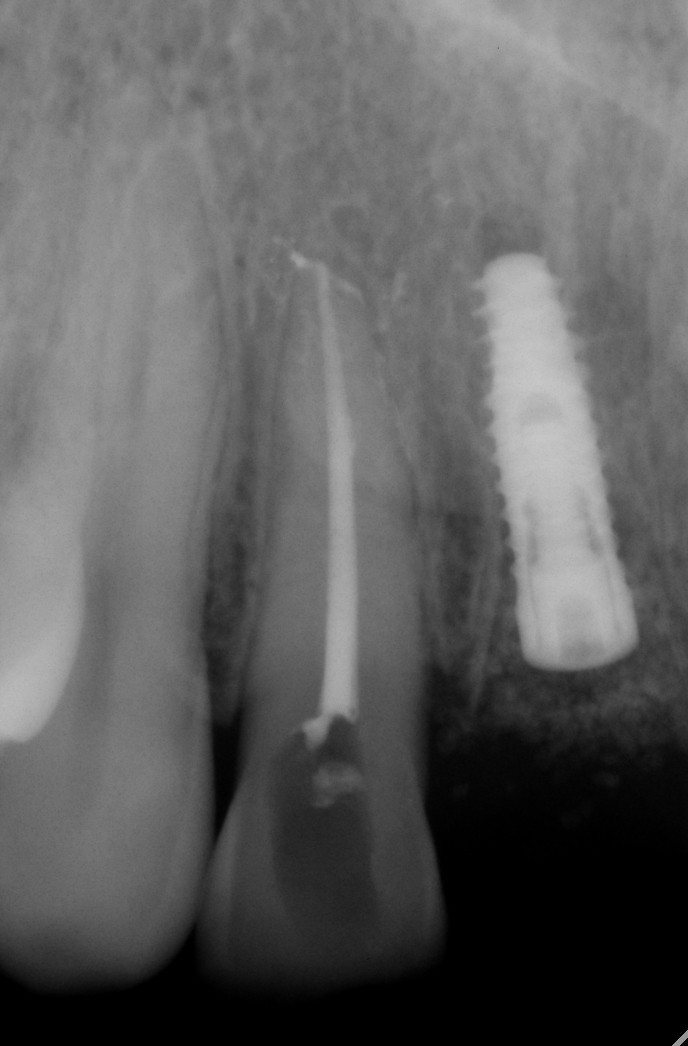

常规开展:数字化根尖片/横断牙合片、数字化口腔曲面体层片、头影测量侧位/正位片、手腕骨片、颅颌面CBCT、牙齿CBCT的检查以及涎腺造影、窦道 瘘管造影。

数字化根尖片